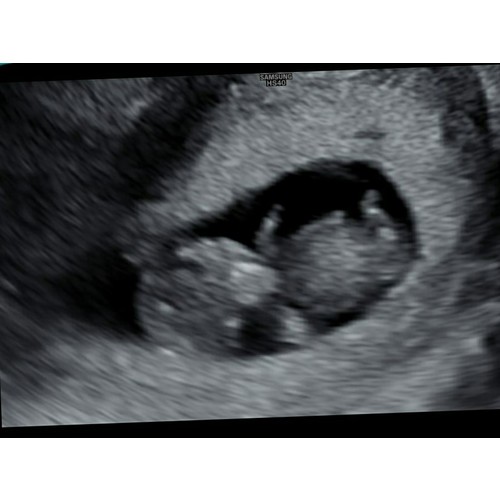

Dit was vrijdag met 10.6. Heel leuk om de armpjes en beentjes te zien bewegen. En echt uitgebreide echo gehad, hebben de doorsnede van de hersenen gezien (dan zie je een soort vlinder) en de maag en blaas (gewoon een zwarte stip 😂). Echt bizar wat er allemaal al in zo’n klein frummeltje zit!